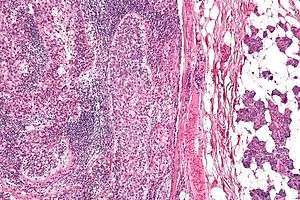

| Micrograph of a sebaceous carcinoma (left of image) metastatic to the parotid gland (right of image). H&E stain. | |

Well-differentiated and moderately differentiated sebaceous carcinoma tend to exhibit vacuolization within the cytoplasm of the tumor cells.[7] Histology may mimic basal cell carcinoma.